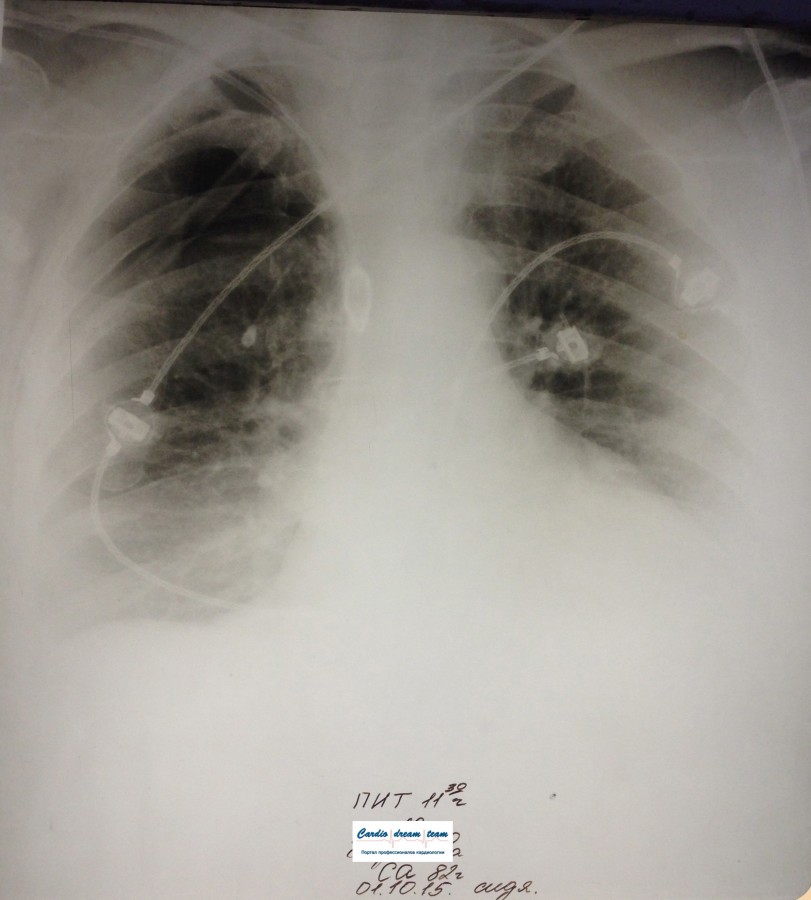

ИССЛЕДОВАНИЕ ОРГАНОВ ГРУДНОЙ КЛЕТКИ Дата 01-ОКТ-15 время 11.30 ОПИСАНИЕ: Проведена рентгенография органов грудной клетки в прямой проекции, положение сидя, условия ПИТ, Р-контроль Легочные поля: Справа легкое расправлено не полностью, апикально до 3го ребра прослеживается свободный газ в плевральной полости. Тень дренажа справа. Тень подключичного катетера в проекции ВПВ. Легочный рисунок: сгущен справа в прикорневой зоне, диффузно деформирован Корни: малоструктурны, обогащены Синусы: нечеткие Сердце: широко лежит на диафрагме (позиционно) ЗАКЛЮЧЕНИЕ: Течение правостороннего пневмоторакса, положительная Р-динамика. Состояние дренирования правой плевральной полости. Р-признаки полнокровия сосудов МКК. Пневмосклероз. Р-контроль .────────────────────────────────────────────────────────────────────── ИССЛЕДОВАНИЕ ОРГАНОВ ГРУДНОЙ КЛЕТКИ Дата 02-ОКТ-15 время 1015 ОПИСАНИЕ:

Проведена рентгенография органов грудной клетки в прямой проекции, положение полусидя, условия ПИТ, Р-контроль Легочные поля: Отрицательная динамика: правое легкое поджато к корню. Тень средостения резко смещена влево. Выраженная подкожная эмфизема мягких тканей грудной клетки справа. Тень подключичного катетера в проекции ВПВ. Легочный рисунок: диффузно деформирован за счет пневмосклероза, сгущен справа Корни: тень средостения смещена влево Синусы: нечеткие Сердце: широко лежит на диафрагме (позиционно) ЗАКЛЮЧЕНИЕ: Правосторонний пневмоторакс, отрицательная Р-динамика. Эмфизема мягких тканей грудной клетки. Пневмосклероз. Р-контроль.